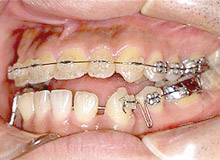

矯正治療前

矯正治療後(完成型)